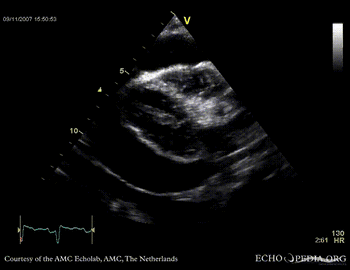

Case 14

Tamponade

Courtesy of:

J. Vleugels, AMC, The Netherlands

tamponade 3